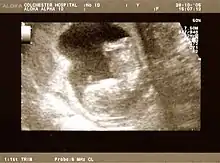

Fetus at 17 weeks

Fetus at 20 weeks

Obstetric ultrasonography is routinely used for dating the gestational age of a pregnancy from the size of the fetus, determine the number of fetuses and placentae, evaluate for an ectopic pregnancy and first trimester bleeding, the most accurate dating being in first trimester before the growth of the foetus has been significantly influenced by other factors.[22] Ultrasound is also used for detecting congenital anomalies (or other foetal anomalies) and determining the biophysical profiles (BPP), which are generally easier to detect in the second trimester when the foetal structures are larger and more developed.[23]

X-rays and computerized tomography (CT) are not used, especially in the first trimester, due to the ionizing radiation, which has teratogenic effects on the foetus.[24] No effects of magnetic resonance imaging (MRI) on the foetus have been demonstrated,[25] but this technique is too expensive for routine observation. Instead, obstetric ultrasonography is the imaging method of choice in the first trimester and throughout the pregnancy, because it emits no radiation, is portable, and allows for realtime imaging.[26]

The safety of frequent ultrasound scanning has not been confirmed. Despite this, increasing numbers of women are choosing to have additional scans for no medical purpose, such as gender scans, 3D and 4D scans.[27] A normal gestation would reveal a gestational sac, yolk sac, and fetal pole.[28]

The gestational age can be assessed by evaluating the mean gestational sac diameter (MGD) before week 6, and the crown-rump length after week 6. Multiple gestation is evaluated by the number of placentae and amniotic sacs present.[29]